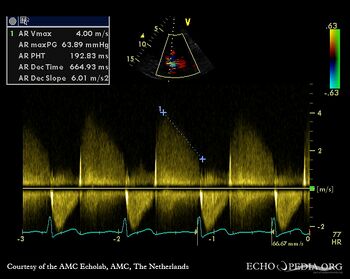

A3CH: Color Doppler, severe aortic regurgitation, excentric jet Continuous-wave signal of severe aortic regurgitation